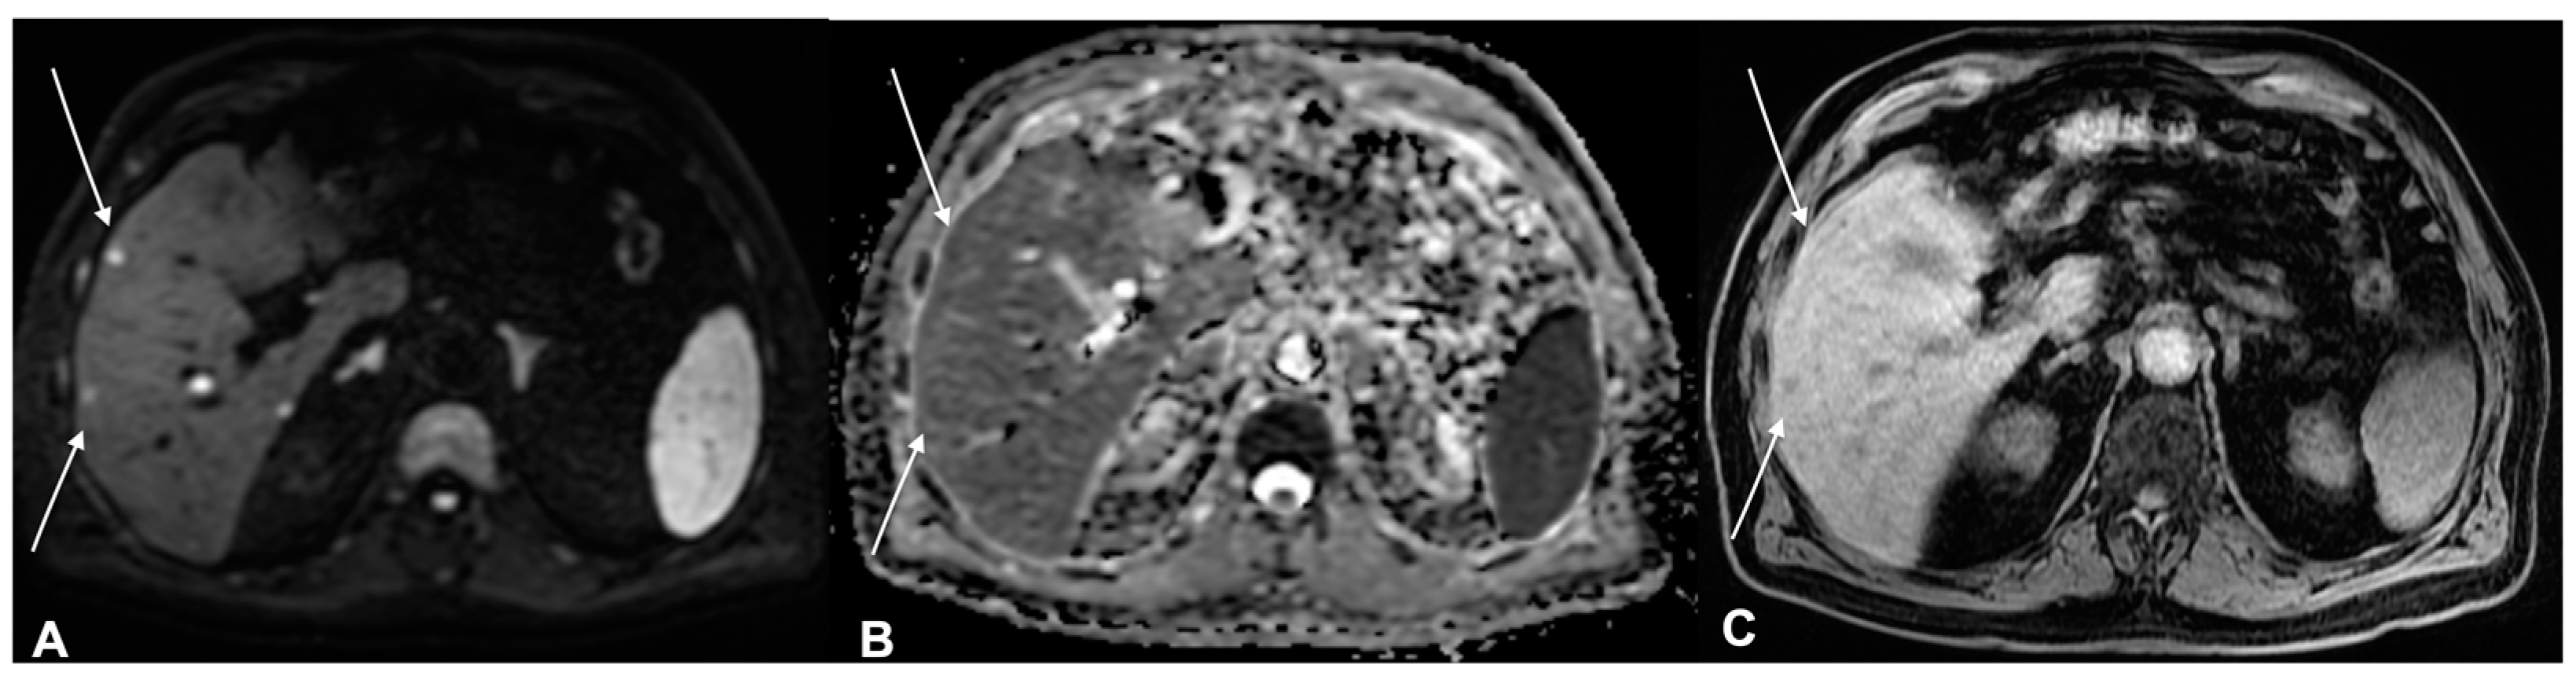

2. Diagnostic Imaging and Non-Melanoma Skin Cancer

3. Diagnostic Tools and Non-Melanoma: Staging and Surveillance